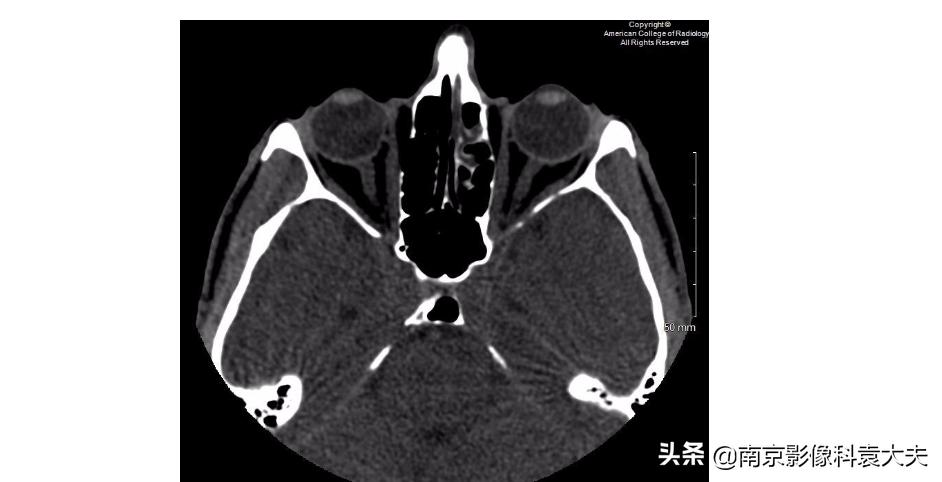

B:右侧眼球外侧的高密度提示出血,这往往是眼外伤的直接征象。

D:一个小的眼外异物位于右侧眼球的表面,它是患者角膜裂伤的一个潜在原因。

上图 在晶状体水平轴位非对比CT图像显示右眼前房(圆环)前后径减小,临床上可在角膜裂伤的情况下看到。

上图 眼球轴位非对比CT图像显示右侧眼睑外侧或巩膜表面可见点状异物(黄圈),发现巩膜上异物,我们应提高对角膜裂伤或其他眼球损伤的怀疑程度。